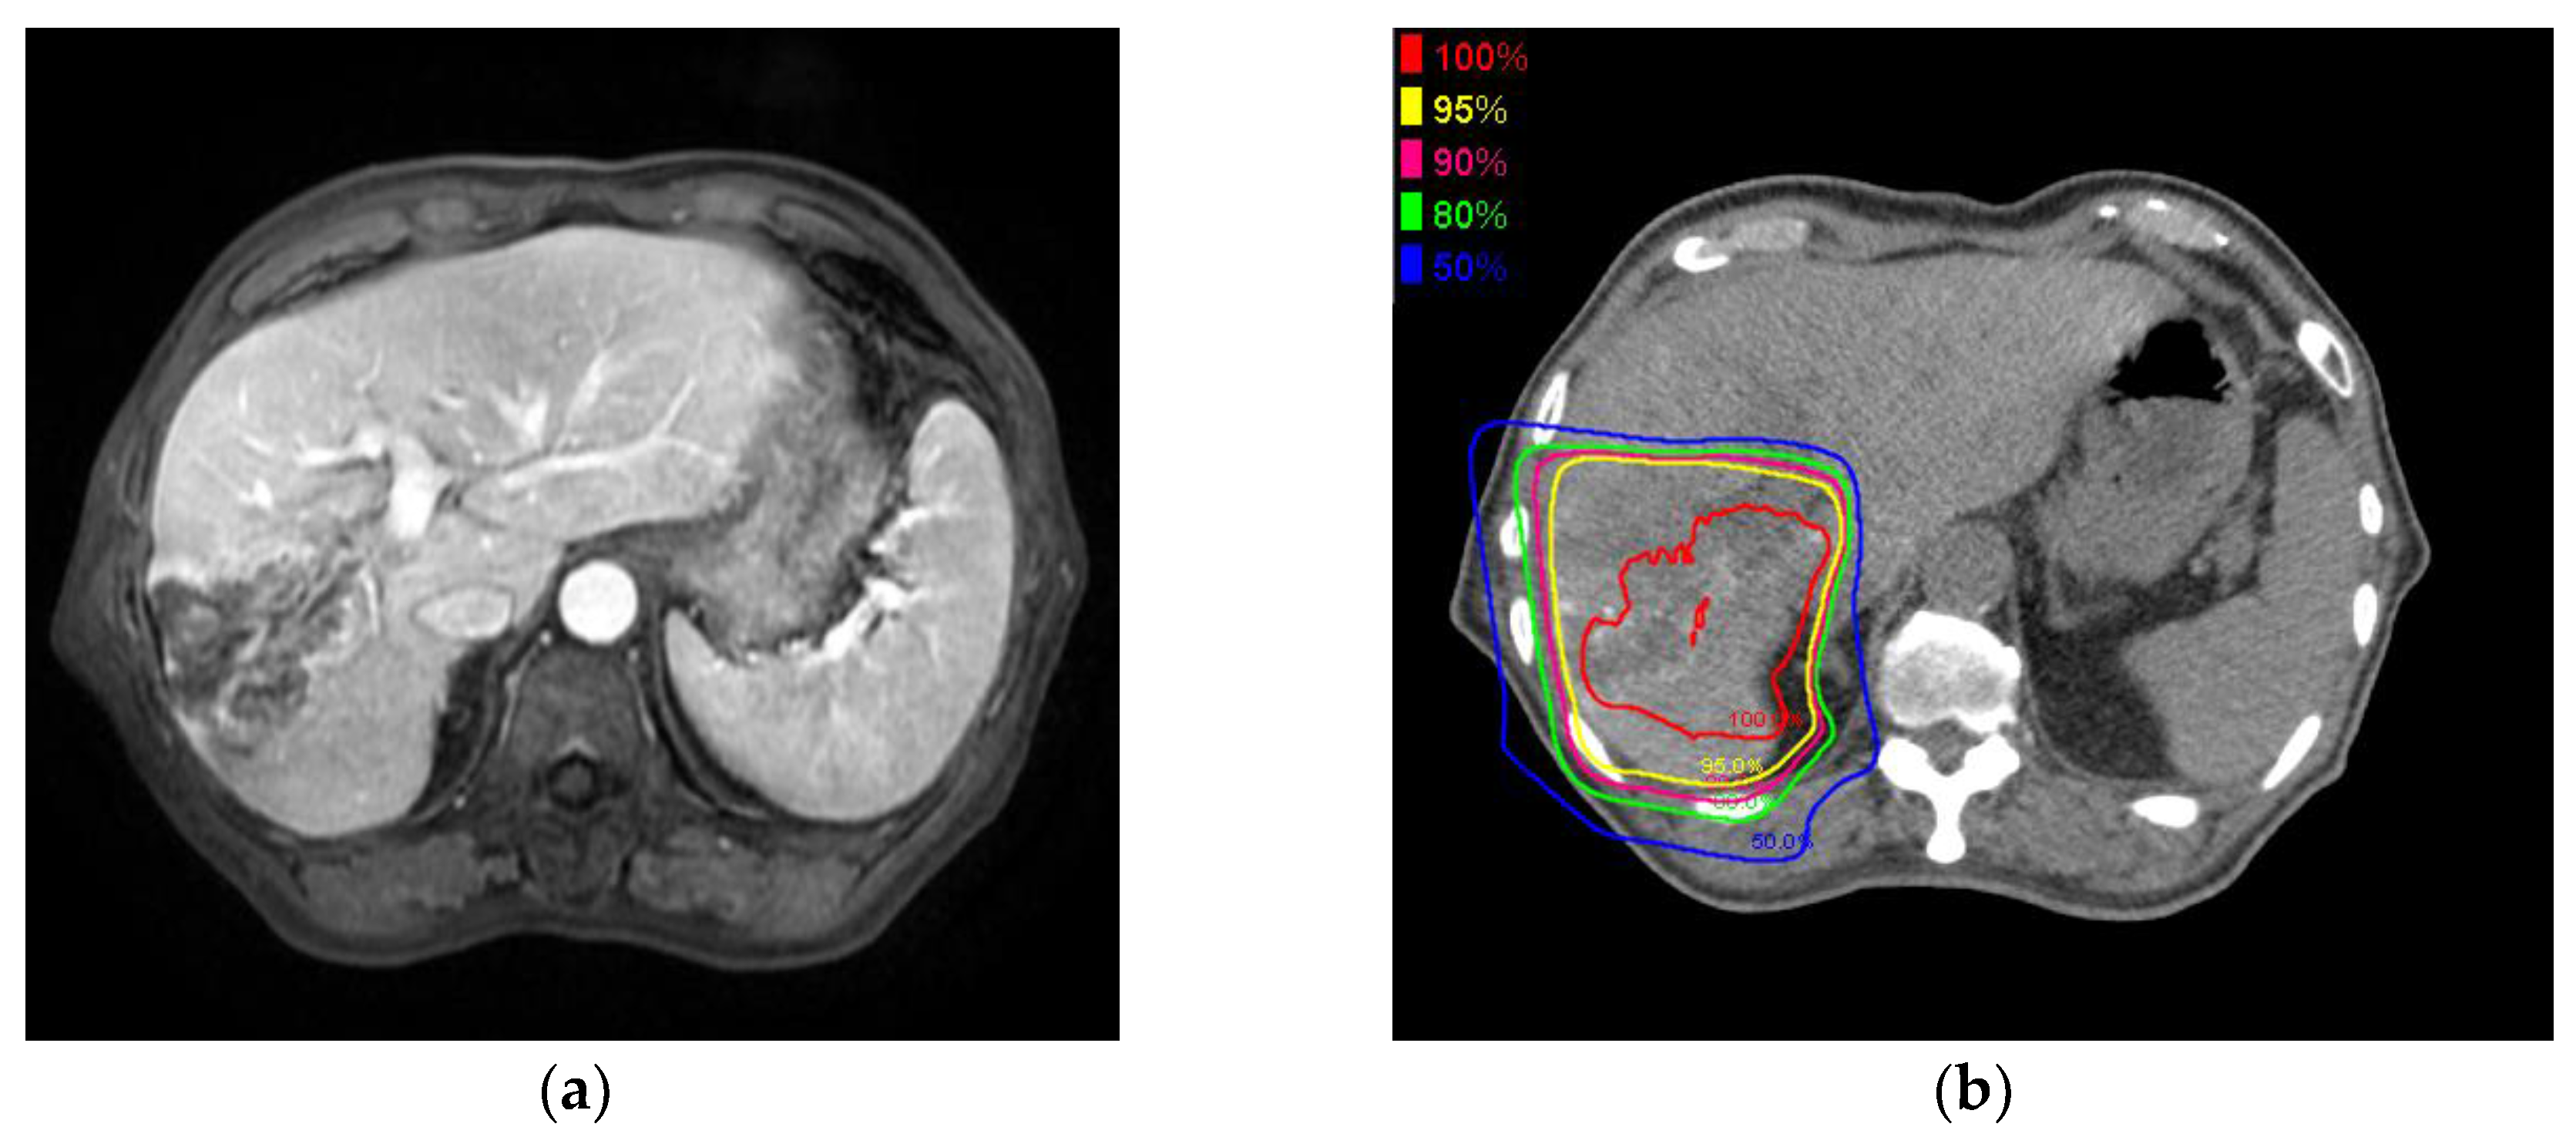

4.2. PBT Planning